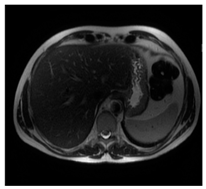

| Ultrasound | ![]() | ![]() | ![]() |